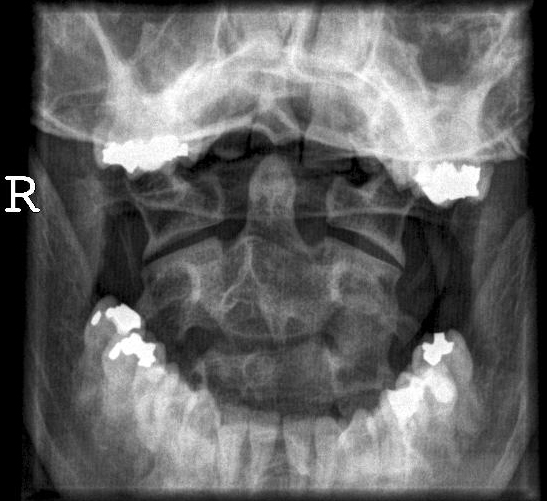

HWS seitlich: wieviel einblenden? | EWMM – Manuelle Medizin

Bild 2/4 – Röntgen: HWS seitlich

Normale HWS Röntgen Stockfoto, Bild: 76782302 – Alamy